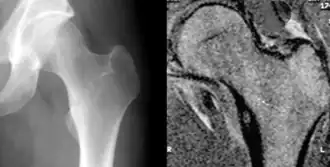

Остео́ид-остео́ма - остеоидная остеома, доброкачественная медленно развивающая опухоль составляет 9-10% среди всех доброкачественных опухолей костей. У мужчин встречается в 4 раза чаще, чем у женщин, болеют преимущественно люди молодого возраста (от 10 до 20 лет).